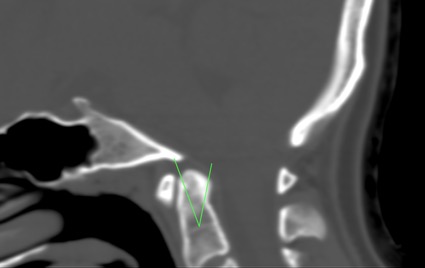

圖1 – 腦頸部CT片

齒狀突畸形一般多是透過腦部或腦頸部CT掃描或是核磁共振進行診斷,透過Thiébaut線、Wackenheim線或Vrousos線進行測量。